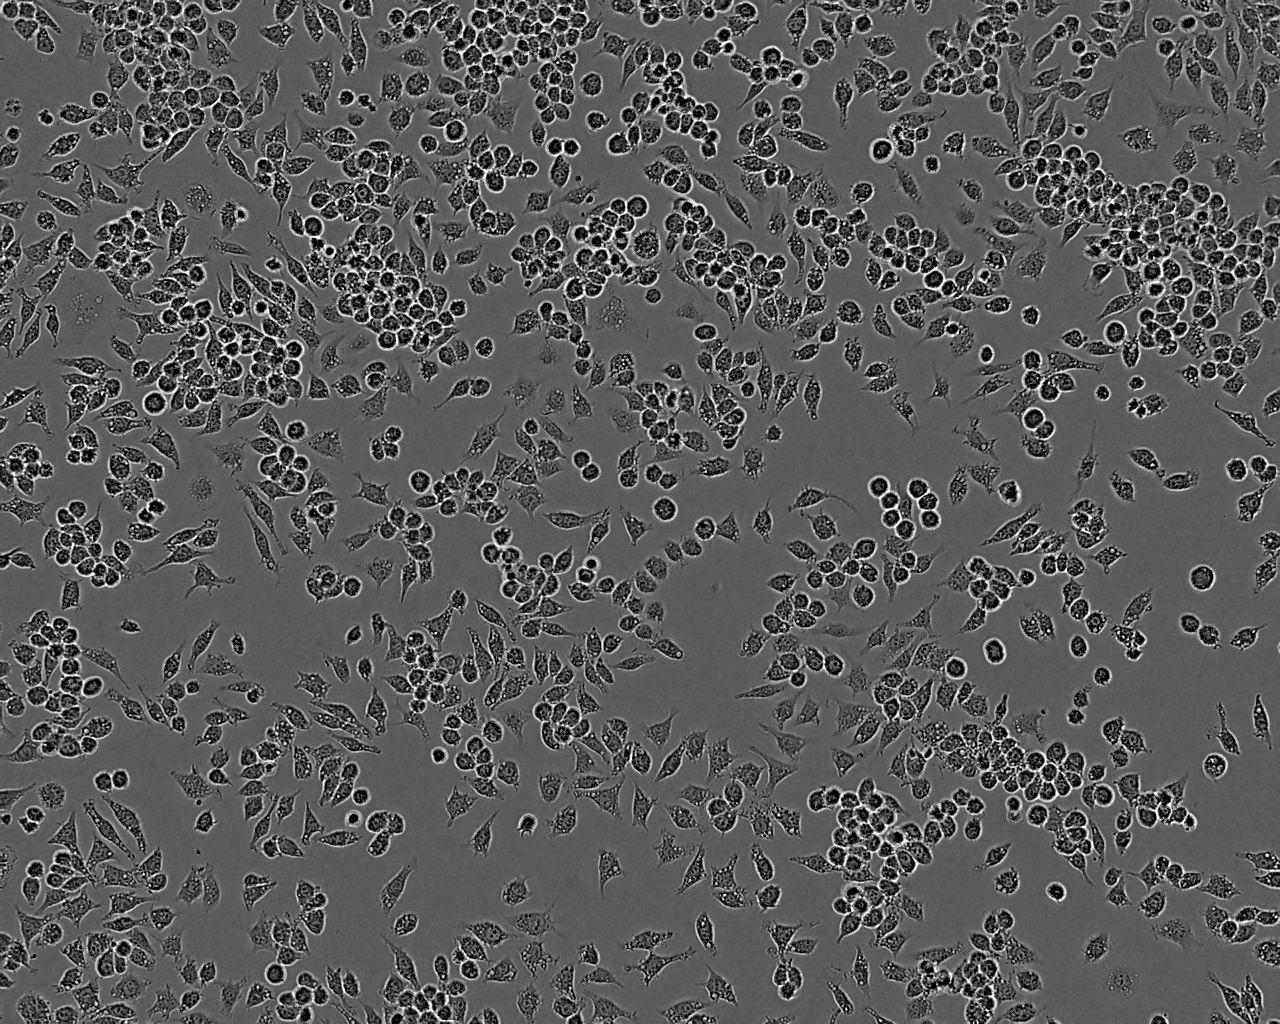

A549-Taxol Cell:人肺癌细胞系

A549-Taxol Cell

细胞形态:上皮细胞样

细胞生长:贴壁

细胞产品包装:复苏形式:T25培养瓶(一瓶)或冻存形式:1ml冻存管(两支)

细胞传代方法:1:2-1:3传代;每周换液2-3次。